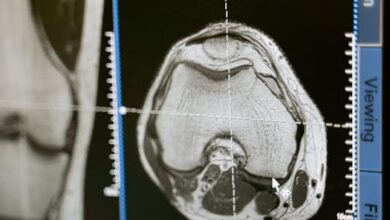

تفسير حلم رؤية الجنين في السونار للمتزوجه

تفسير حلم رؤية الجنين في السونار للمتزوجة رؤية الجنين في السونار في المنام: دلالات وتفسيرات رؤية الجنين في السونار في…